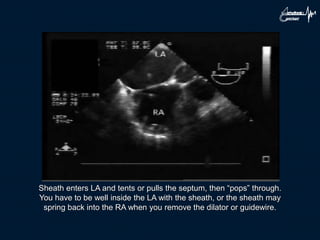

Sheath enters LA and tents or pulls the septum, then “pops” through.

You have to be well inside the LA with the sheath, or the sheath may

spring back into the RA when you remove the dilator or guidewire.